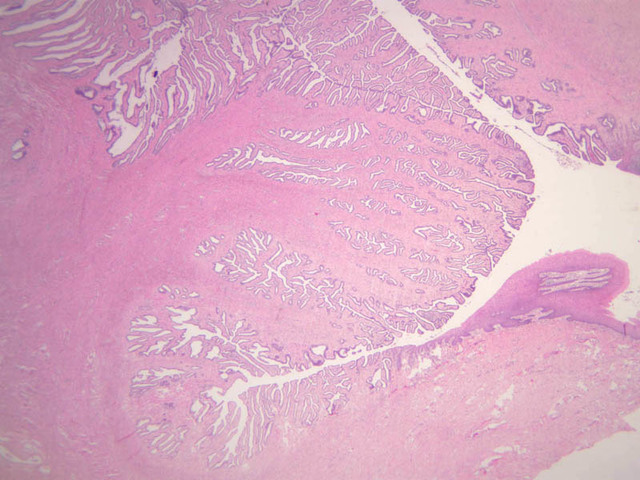

After ovulation, the oocyte passes into the uterine tube (i.e. oviduct, i.e. fallopian tube). Fertilization takes place here. This tube is subdivided into four regions:

The wall of the uterine tube consists of three layers; a mucosa, a muscularis, and an adventitial/serous coat (B-96 [2.5x, 10x-labeled, 20x, 40x] [2.5x, 10x, 20x, 40x]; B-97, monkey uterus [2.5x, 10x, 20x, 40x]). The mucosa is organized into folds that vary in their degree of complexity with the tube regions. The mucosa is lined by a simple columnar epithelium consisting of two cell types, ciliated and non-ciliated, secretory (B-93 [10x, 20x, 40x-labeled]). The mucosal lamina propria consists of somewhat loose connective tissue and is highly vascular. No muscularis mucosae are present. The muscularis consists of two layers of smooth muscle, the inner being oriented in a circular fashion and the outer longitudinally.

The structure of the uterine tube is under the control of, and responds to, cyclic changes in the levels of steroid hormones. Structural alterations to provide favorable transport for the oocyte commence anew with the beginning of each cycle and peak at mid-cycle just before ovulation. These include increases in height and number of the ciliated cells as well as active secretion in the secretory cell. For the remainder of the cycle thereafter, dedifferentiation occurs. The cyclic changes occur to a greater extent in the upper ampulla and infundibulum. The margin of the infundibulum is drawn out into numerous finger-like processes called fimbrae. Microscopic examination of these will reveal that within the lamina propria are numerous large blood vessels, especially veins, as well as bundles of smooth muscle forming an intervening network. At the time of ovulation, the vessels become enlarged with blood, causing turgidity, which when combined with smooth muscle contraction brings the infundibular opening into close apposition with the ovarian surface.